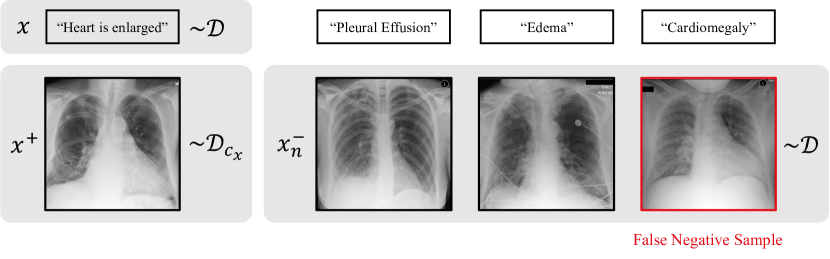

Figure 1: False negatives in paired image-text data. Drawing negative image samples xnsuperscriptsubscript𝑥𝑛x_{n}^{-} from the data distribution 𝒟𝒟\mathcal{D} may result in samples that are semantically similar to the text x𝑥x (“Heart is enlarged” and “Cardiomegaly” imply the same pathology). False negative samples occur at an uneven rate (e.g., depending on the pathology type) and degrade the performance of image-text models on downstream tasks.

When training an image-text model using contrastive learning, each text is positively paired with the associated image from the same imaging event and negatively paired with a batch of images uniformly drawn from the training data set (Li et al., 2019; Lu et al., 2019; Chen et al., 2020; Radford et al., 2021; Liao et al., 2021; Zhang et al., 2022b; Wang et al., 2023). If a negatively paired image is semantically similar to the text, it is considered as a false negative (Saunshi et al., 2019), as illustrated in Figure 1. It has been shown previously that false negatives cause a substantial decline in downstream classification performance when using image representations trained with contrastive learning (Chuang et al., 2020).